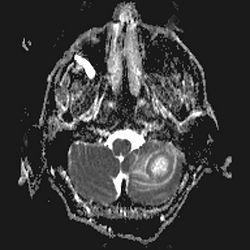

Diffusionsvægtet MR-skanning

DWI ADC

En absces er hvid (White) på DWI (Diffusion Weighted Imaging, det samme som isoB1000) og sort (Dark) på ADC (Apparent Diffusion Coefficent).